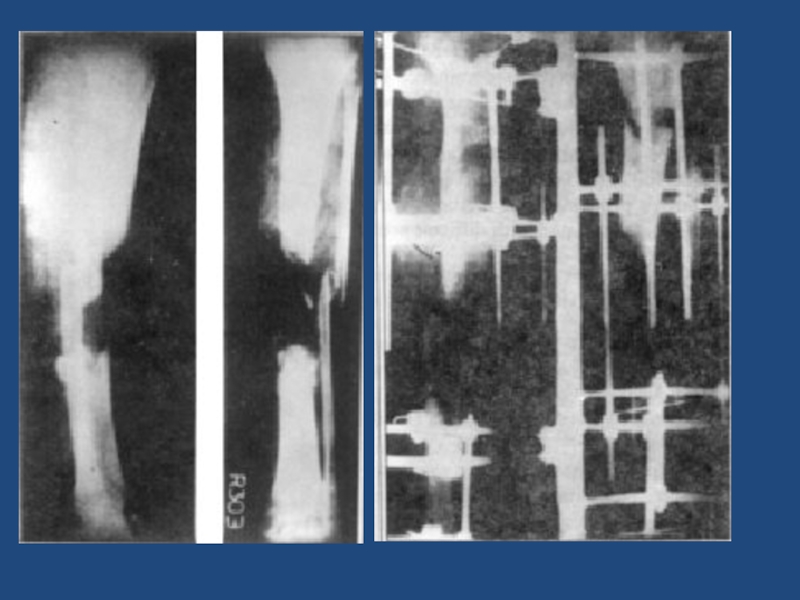

Слайд 5554

Срастающийся перелом с/3(н/3)б/б кости. (ложный сустав)Центромедулярный блокирующий остеосинтез

54Срастающийся перелом с/3(н/3)б/б кости. (ложный сустав)Центромедулярный блокирующий остеосинтез